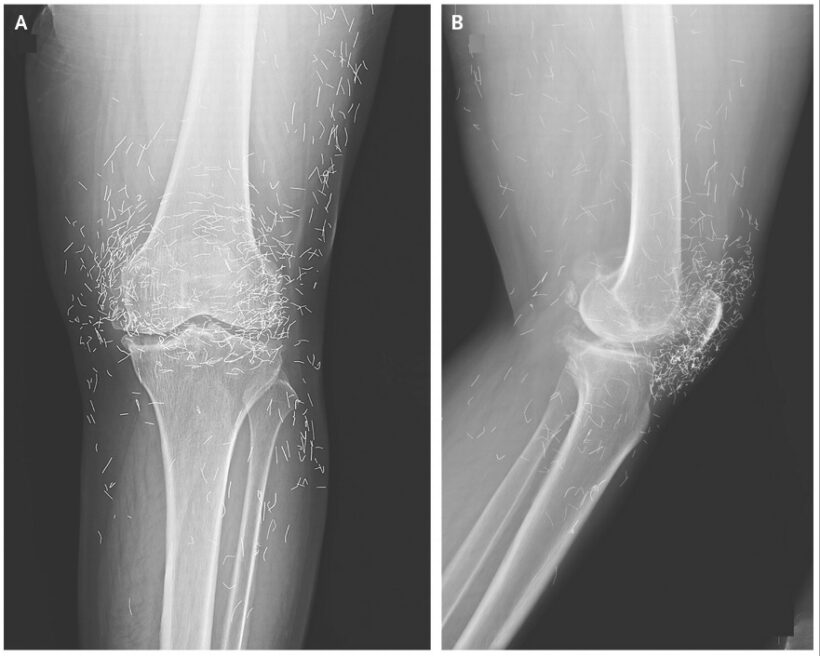

4. Повреждение сустава из-за акупунктуры

Женщина с остеоартритом колена начала регулярно посещать сеансы акупунктуры, так как обезболивающие вызывали у неё проблемы с желудком. Однако вскоре её колени сильно опухли и заболели. Рентген показал утолщение костной ткани и образование остеофитов в суставах и большеберцовых костях. Кроме того, вокруг обоих коленных суставов были видны сотни мельчайших частиц. Оказалось, что акупунктурист намеренно оставлял в её коленях золотые нити в качестве части лечения. В других случаях такие нити, мигрируя в теле, вызывали кисты и повреждения тканей.